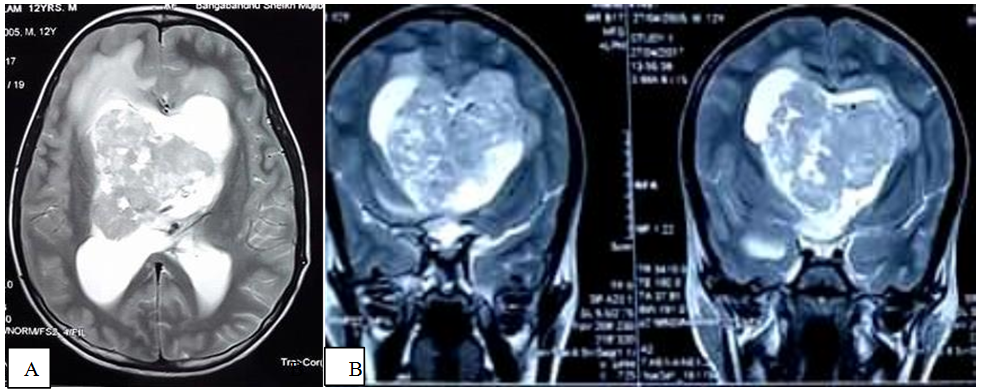

A 12 years old male patient presented with insidious onset of dull aching headache and vomiting for one year, progressive dimness of vision in both eyes for the same duration (Figure 1). He experienced one episode of generalized tonic clonic convulsion followed by loss of consciousness. After evaluation with MRI of brain, he diagnosed as a case of SEGA with obstructive hydrocephalus and underwent urgent VP shunt surgery in a private hospital (Figure 2). However, 7 months following shunt surgery, patient admitted for definitive surgery into BSMMU with additional features of ascites. However, his liver function test, renal function test and cardiac evaluation were normal. Serum albumin, total protein and albumin- globulin ratio was also within normal limit. At this stage, we exteriorize the lower end of VP shunt and drain 1 litre ascitic fluid for decompression. We sent both CSF and ascitic fluid for biochemical, cytological and microbiological examination. Findings were normal except high protein level both in CSF and ascitic fluid. Later on, we came into conclusion that, CSF high protein level was responsible for impaired peritoneal absorption of CSF. Patient underwent anterior interhemispheric transcallosal approach and gross total removal of tumor. At 10th POD, he underwent right sided ventriculo-atrial shunt. His postoperative period was uneventful. 1 year after surgery, repeat MRI of brain with contrast showed no recurrence of tumor with well functioning status of the shunt (Figure 3).

Figure 2 MRI of brain , T2WI demonstrates a heterogeneously hyperintense lesion occupying both lateral ventricle as well as third ventricle with multiple intrinsic flow voids (A, B, C).